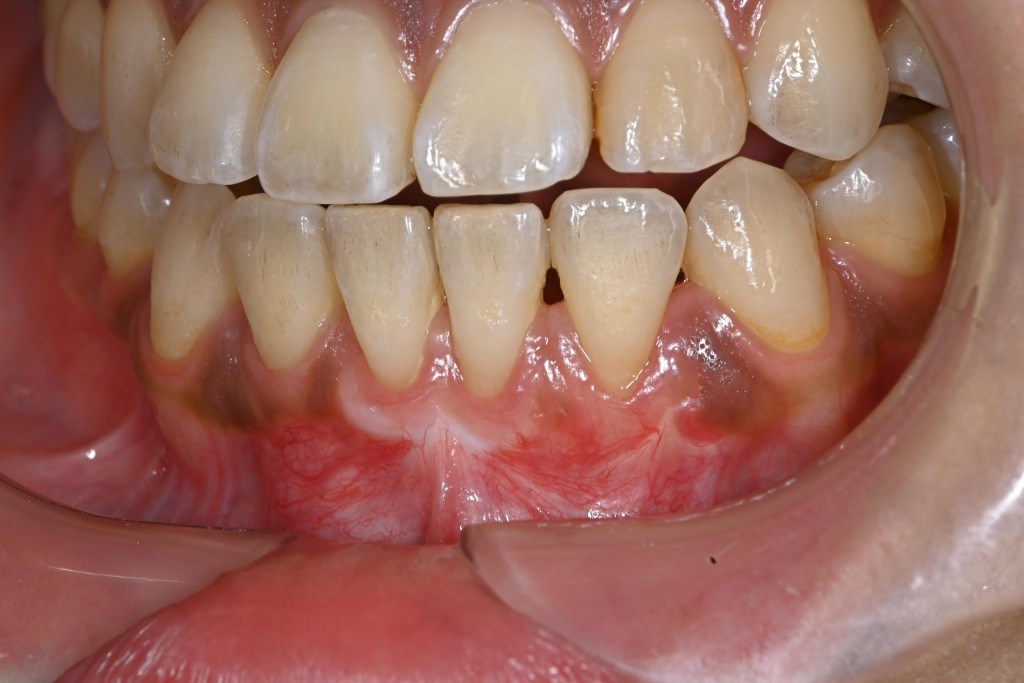

さて今回は下顎の歯肉退縮の症例を紹介します。

| 治療内容 | 歯肉退縮治療(VISTA) |

| 治療期間 | 3ヶ月 |

| 治療費用 | 17万円( 税抜 ) |

| 副作用・リスク | 外科処置が伴うため、術後の疼痛・腫脹・出血・咬合痛などを生じる事があります。 麻酔を行う場合、腫れやむくみを生じる事があります。 |